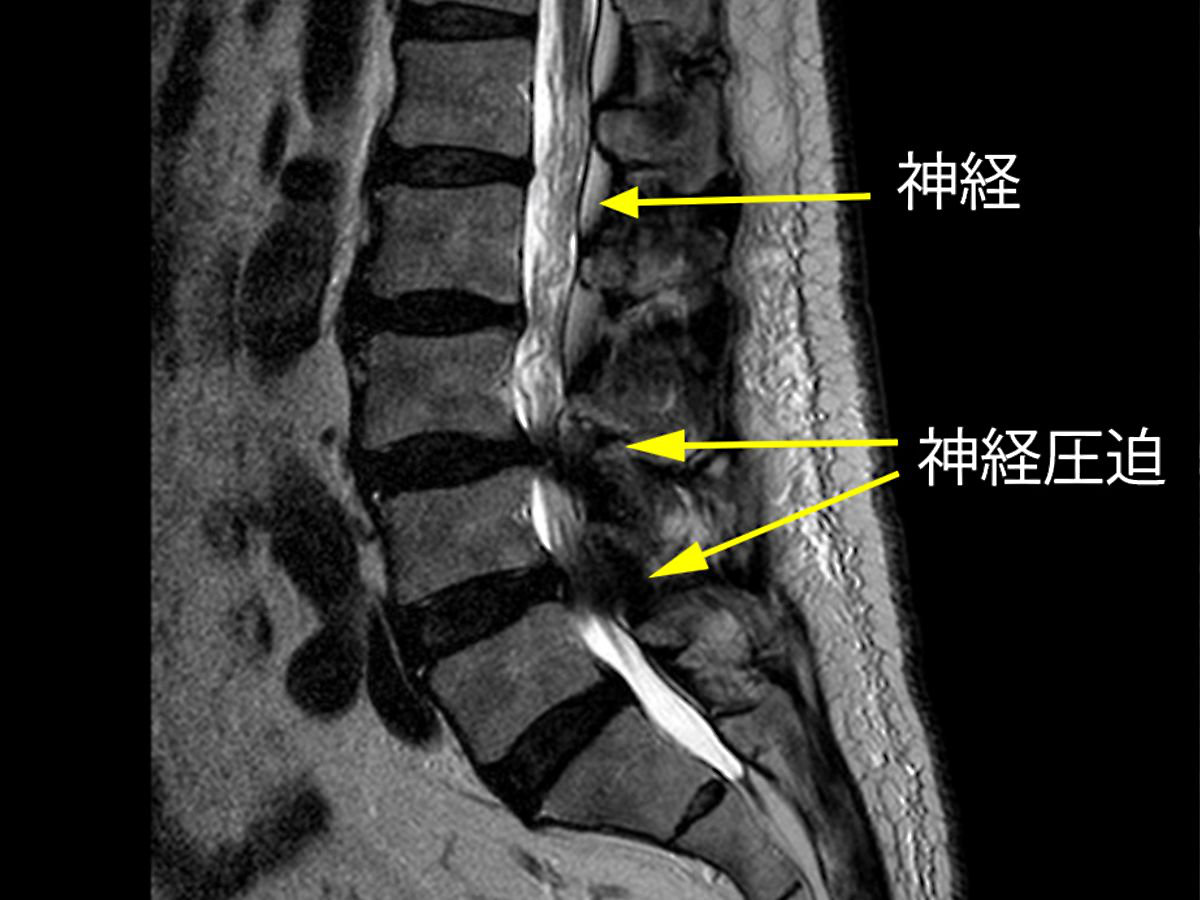

腰椎のレントゲンで、腰椎の並び方、変形を調べます。また身体を動かしながら撮影することで不安定な脊椎があるかを調べます。腰椎MRI検査では神経を写すことができます。MRI検査で神経の圧迫の有無、または骨折や腫瘍など他の疾患の診断が可能であり、腰部脊柱管狭窄症の検査では欠かせない検査です。しかし体内に金属がある方はMRI検査ができないことがあります。その場合や、より詳細な検査が必要な場合は、脊髄造影検査を行うこともあります。